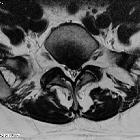

Disc protrusions are a type of disc herniation characterized by protrusion of disc content beyond the normal confines of the intervertebral disc, over a segment less than 25% of the circumference of the disc. The width of the base is wider than the largest diameter of the disc material which projects beyond the normal disc margins. The protrusion must not extend above or below the relevant vertebral endplates .

A disc protrusion is also described in terms of its axial position, into central, subarticular, foraminal, extraforaminal, or anterior locations .

Additionally, the terms contained (outer annulus fibrosus laminae are intact) and non-contained (all laminae are deficient) are also sometimes used .